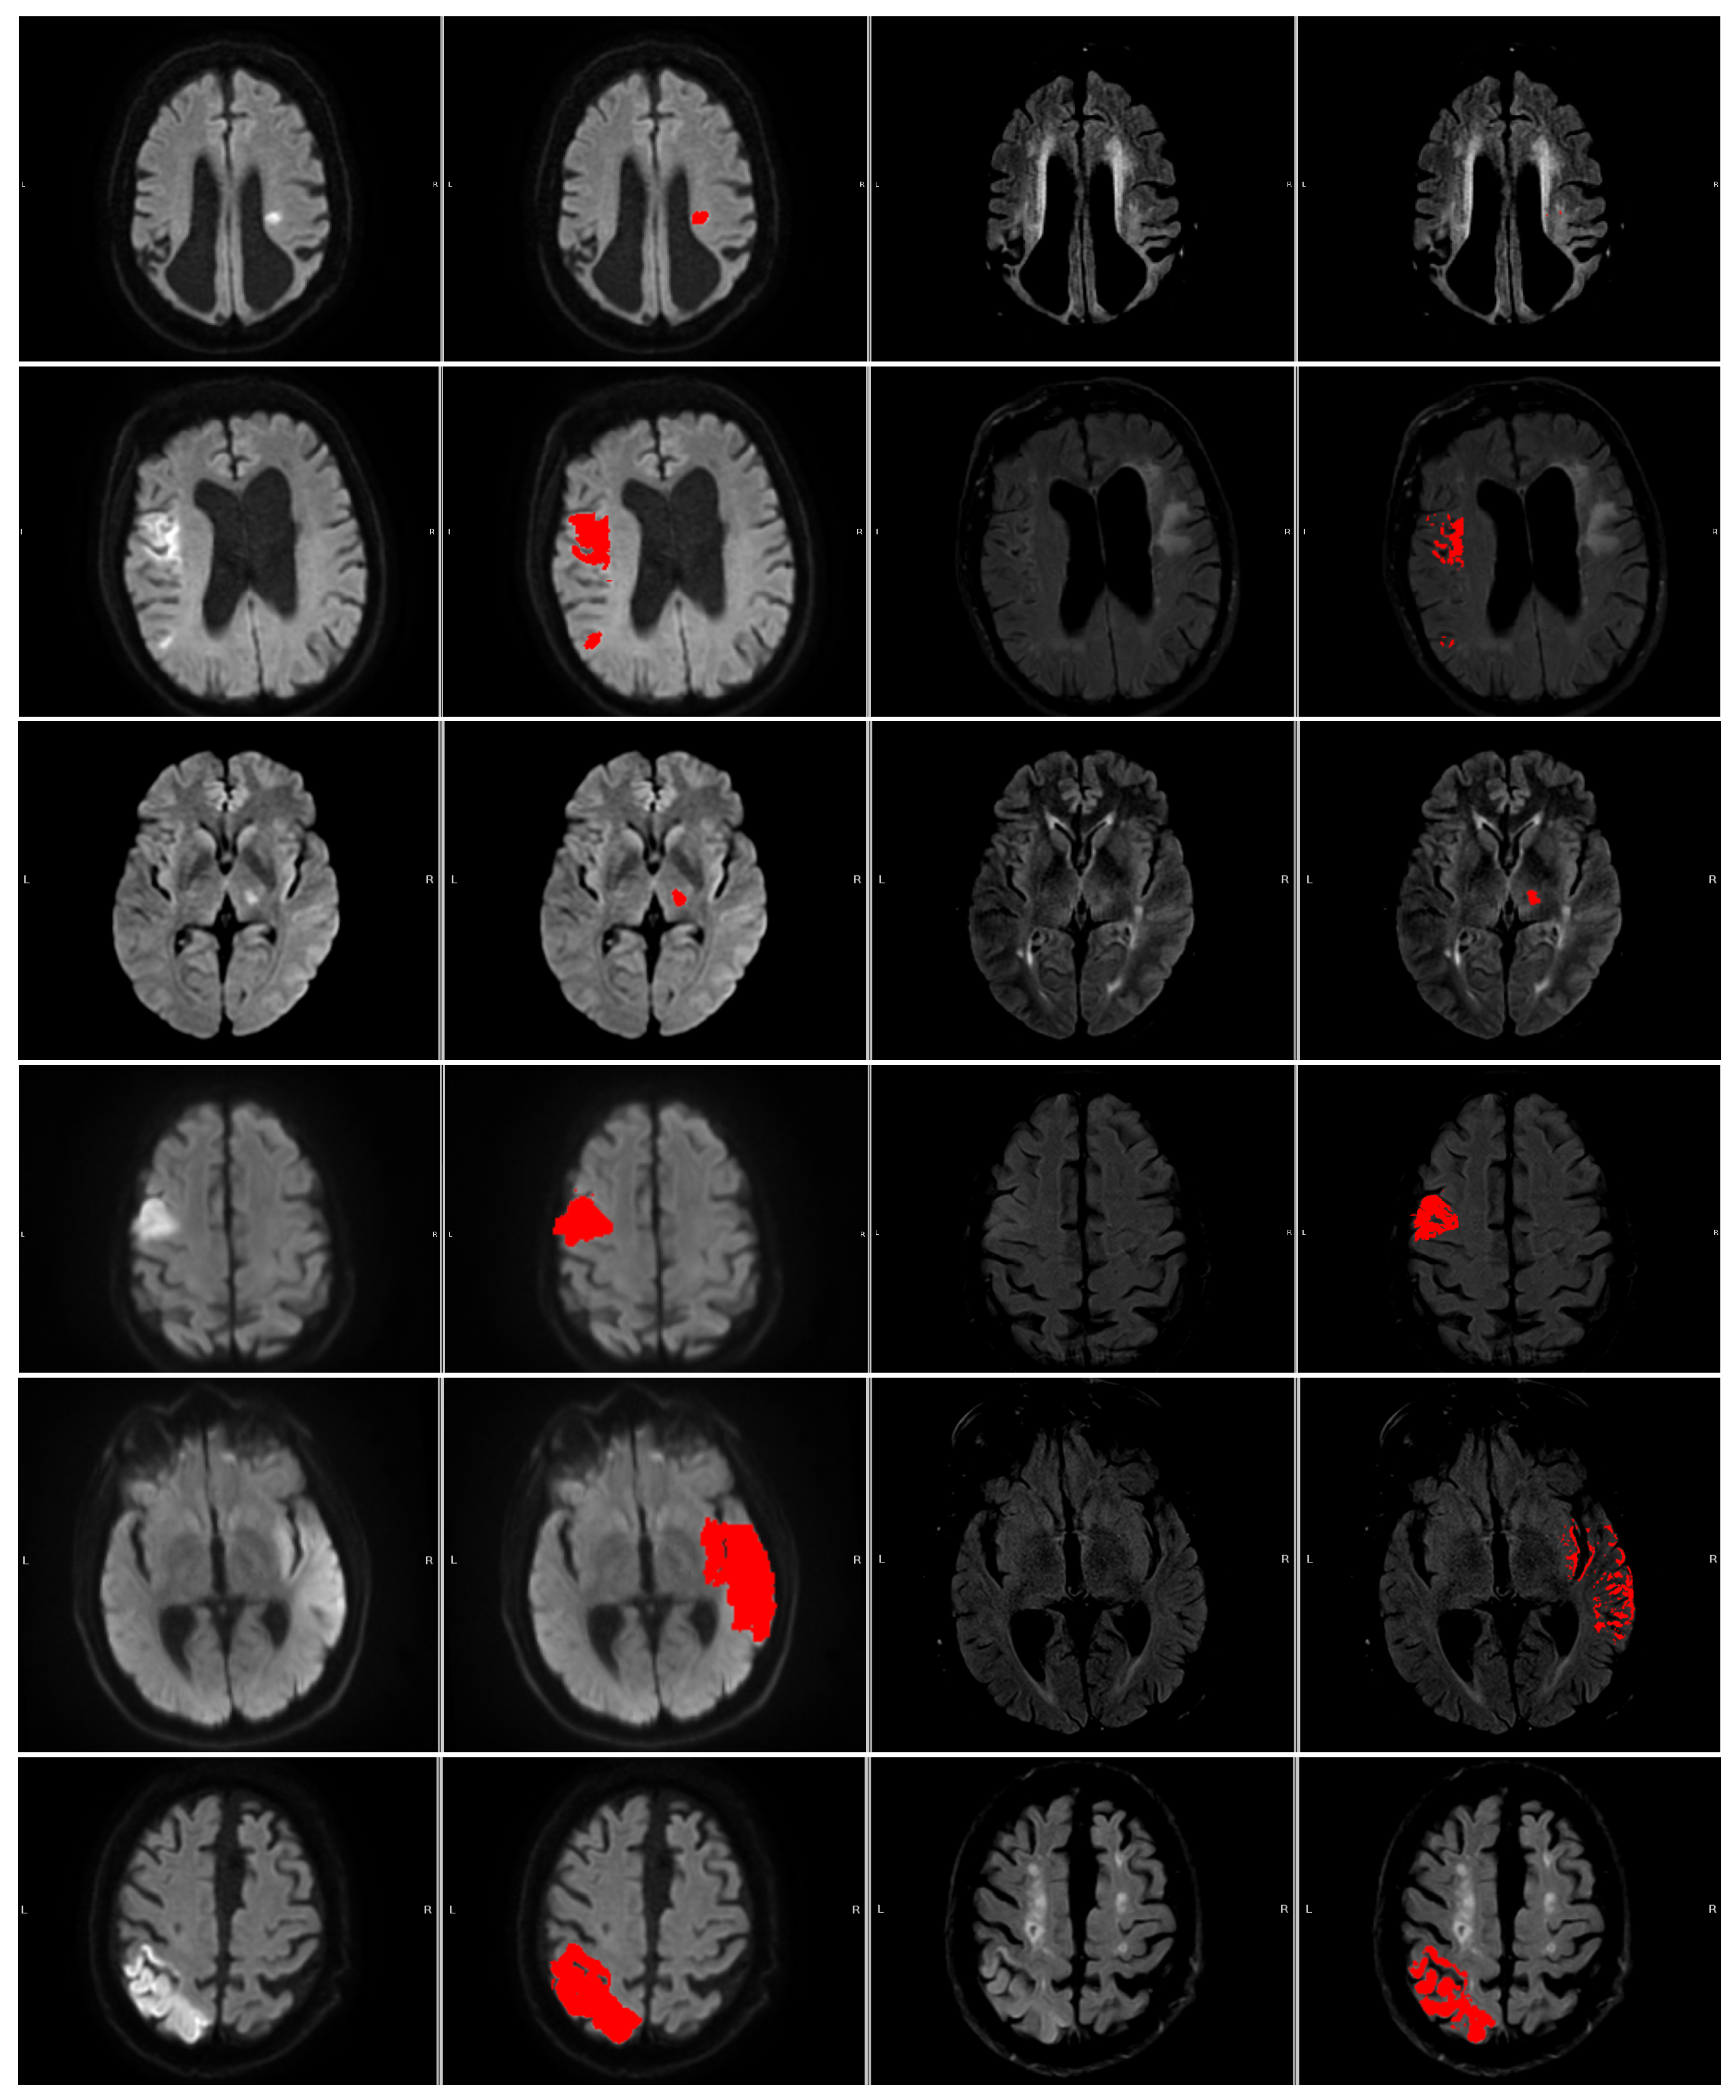

Figure 5. The numbered outlier cases from Figure 4. The cases are presented in ascending order 1 (top) through 6 (bottom). All cases are shown as (left to right) DWI (b1000), DWI (b1000) with segmentation (red area), FLAIR, and FLAIR with segmentation (red area).

The 6 numerated cases can be seen in Figure 5. Case 1 is a situation where both the area of interest and the contralateral side are slightly hyperintensive, leading to a small DWI/FLAIR mismatch ratio but large intensity measure and a no-mismatch assessment in the clinic. In Case 2, part of the contralateral side is hyperintense, which may lead to slight under-segmentation. However, the contralateral hyperintensity is not large enough to be clear from the intensity measure. Cases 3 and 4 correspond to two cases where the patients are deemed to be mismatch cases at the hospital, but our measures disagree. Case 5 shows a mismatch assessed case where the measures agree. Case 6 shows a no-mismatch assessed case where the measures and the assessment agree. Furthermore, the case shows the relevance of our criterion that the intensity be brighter than the mean plus 0.25 standard deviations, as part of the contralateral side is hypo-intense.